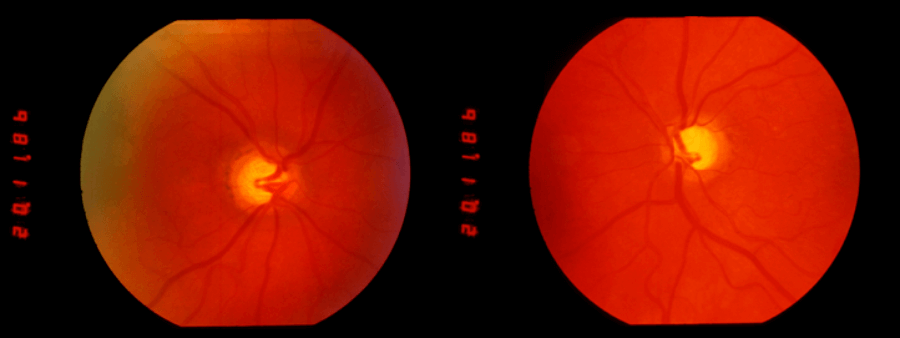

Prof Dott also recorded optic disc cupping on direct ophthalmoscopy which he considered congenital, this diagnosis being confirmed 61 years later when I examined her and the photographs (Figure 2) were taken. So much for modern OCT etc. and how many neurosurgeons now use an ophthalmoscope?

Figure 2: Optic disc photographs taken in 1988 illustrating the congenital cupping first diagnosed in 1927.